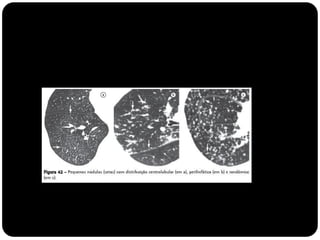

 Figura do “Computed Tomography of the lung...”(Baert 2007)

Lóbulo pulmonar secundário

Menor porção do pulmão, ainda circundada por um septo de

tecido conjuntivo;

Composto por 3 a 5 bronquíolos terminais (3 a 12*)

Identificado na TCAR tanto em estados normais quanto

patológicos;

Revestidos por septos interlobulares que contém as tributárias das

veias periféricas e dos vasos linfáticos;